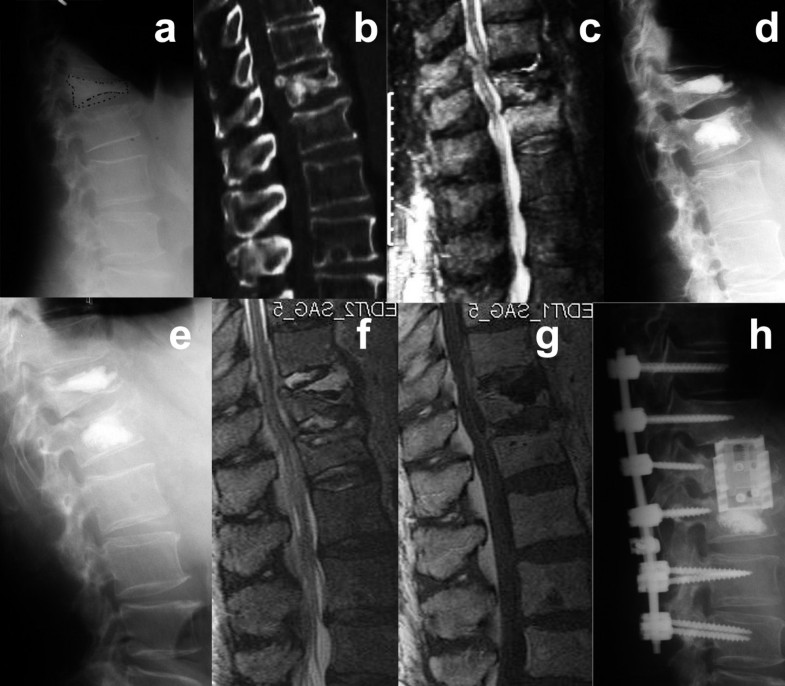

(PDF) Recurrence of Local Kyphosis After Percutaneous Kyphoplasty The

(PDF) Recurrence of Local Kyphosis After Percutaneous Kyphoplasty The, 2%), bed rest (46% vs. In the united states, more than 700,000 osteoporotic vertebral compression fractures occur each year.